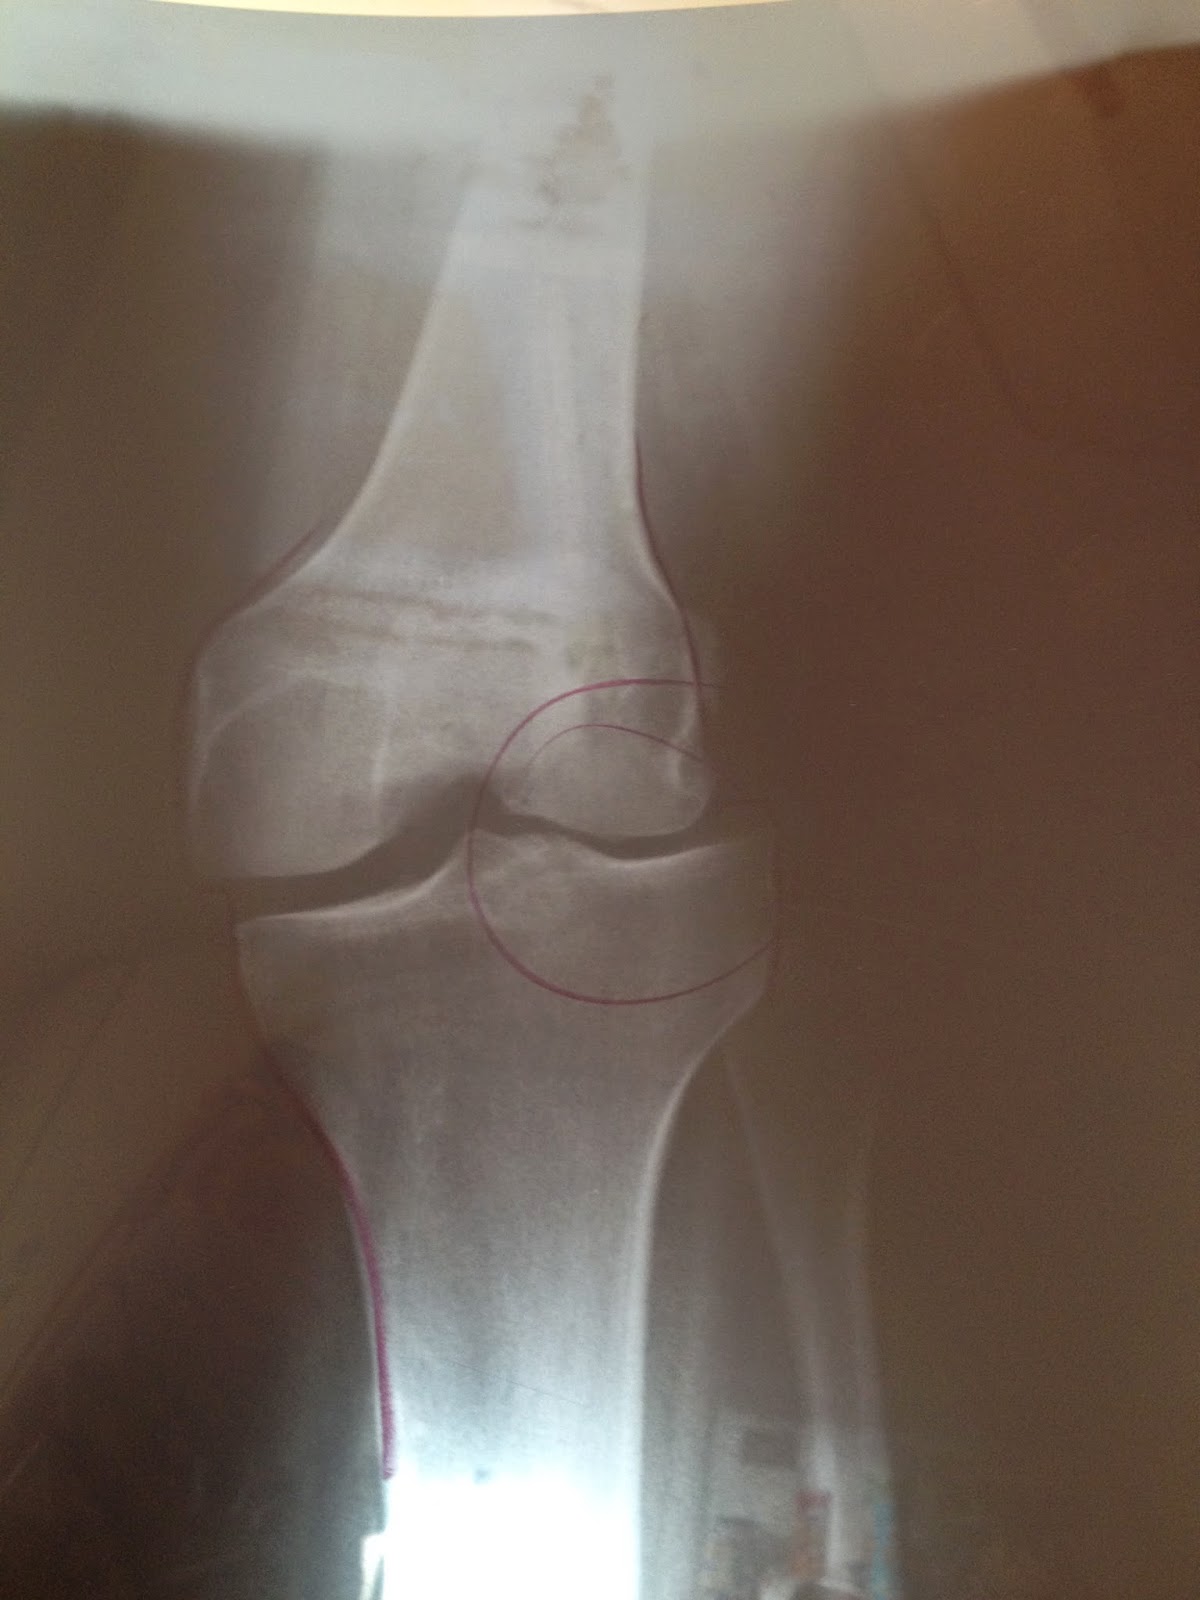

My right knee is misaligned as you can see from this X-ray. It is a little off center and I had been having a problem with it being sore off and on for years.